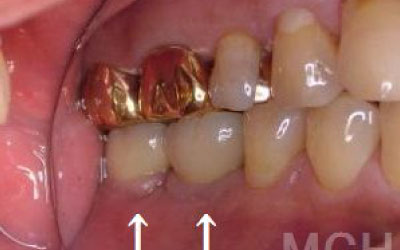

噛み合わせの力の60%以上がこの奥から2つの歯で支えているので、ここをしっかりインプラントで治療するのはお勧めです。

骨が薄い場合は、そのままインプラントすることはお勧めできません。

ただ、事前に骨を増やす治療をしたり、インプラントと同時に骨を増やす治療をしたりすればインプラントをすることは可能です。

1)インプラント治療を行う前に、骨の治療が必要かもしれません。

2)骨の治療から始めると、その分、治療期間が長くなります。

3)骨の治療は、通常のインプラント治療よりも難易度が高いため、経験の豊富な先生やインプラント認定医のいる歯科医院で治療を受けることをお勧めします。

4)骨の状況をしっかり把握するためにも、CT撮影が必須となります。